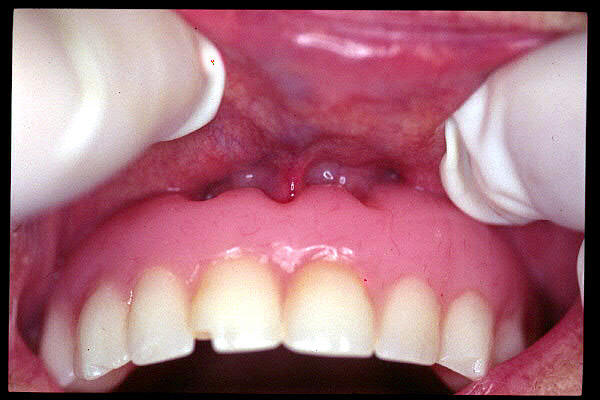

CM Hipertrofia de glándula sublingual